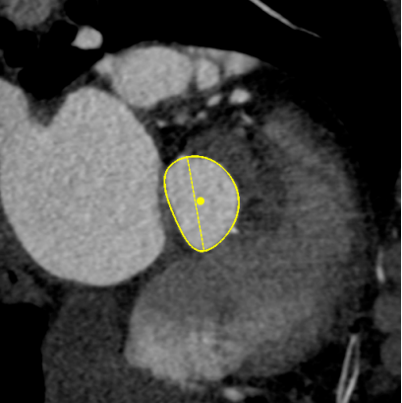

30%收缩期

Annulus

长径: 24.8 mm

周长: 68.6 mm

面积: 352.3 mm²

LVOT

长径: 24.3 mm

周长: 66.3 mm

面积: 321.7 mm²

SOV

27.3 x 25.8 x 25.9 mm

STJ

长径: 27.6 mm

周长: 84.4 mm

面积: 566.2 mm²

高度: 13.8mm

RCA

下缘高度 10.2mm

上缘高度 11.9mm

瓣叶长度 12.7mm

LCA

下缘高度 7.1mm

瓣叶长度 11.8mm